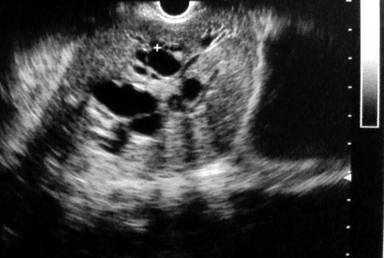

A previously well 24-year-old male presented with a one month history of rapidly progressive obstructive jaundice associated with abdominal pain suggestive of a biliary colic. He was otherwise well except for anorexia of the same duration. His past medical and family history were unremarkable except for receiving treatment for meningitis two years back. General examination revealed he was deeply icteric, but free of supraclavicular lymphadenopathy and features of chronic liver disease. Abdominal examination showed tender hepatomegaly with a palpable gallbladder but no free fluid. His liver functions were deranged with significantly elevated serum bilirubin and alkaline phosphatase levels. Trans-abdominal ultrasonography showed a suspicious pancreatic head mass, a dilated common bile duct (1.8 cm) and a distended gallbladder with no calculi. Contrast-enhanced CT (CECT) of the abdomen revealed a pancreatic head mass encircling the main pancreatic duct and CBD opening. Tumor also extending into the duodenal wall through muscularis propria without evidence of superior mesenteric or portal vessel involvement nor distal metastases. The pancreatic duct showed significant dilatation but there was no intraductal parenchymal calcification (Figures 1 and 2). These findings were corroborated by upper gastrointestinal endosonography. Pre-operative ERCP and stenting was done for nutritional optimization prior to surgery. Based on a preoperative diagnosis of an ampullary malignant stricture a standard pancreaticoduodenectomy (Whipple’s procedure) was performed. During surgery, the entire pancreas was found to exhibit a hard texture but there was no evidence of peritoneal or liver metastases. Postoperative recovery was uneventful except for a minor (ISGPF – grade A) pancreatic fistula which resolved with conservative management. The resected specimen (Figure 3) showed an irregular, solid, whitish mass measuring 4.4x3.0x3.0 cm. Histology demonstrated a lesion composed of nests of small round cells with scanty cytoplasm surrounded by prominent desmoplastic stroma, compatible with a poorly differentiated DSRCT of the pancreatic head (Figure 4). The resection margin was positive and there was perineural and vascular invasion. The tumor cells were negative for synaptophysin and chromogranin but positive for desmin and cytokeratin (Figure 5). Peripancreatic lymph nodes were positive for the tumor deposits. He received adjuvant combination chemotherapy that included vincristine, cyclophosphamide, doxorubicin, ifosfamide and etoposide. Clinical assessment and CECT done six months after surgery showed him to be well with no evidence of disease progression.

Figure 1. Upper GI endoscopic ultrasound showing pancreatic head mass. |